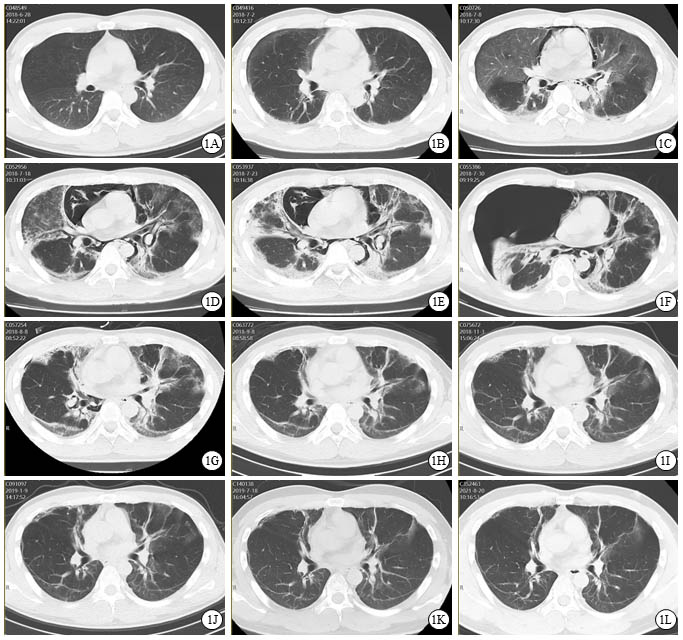

图 1 患者口服百草枯后胸部CT影像学变化

2018-06-28 CT图

2018-07-02 CT图

2018-07-08 CT图

2018-07-18 CT图

2018-07-23 CT图

2018-07-30 CT图

2018-08-08 CT图

2018-09-08 CT图

2018-11-03 CT图

2019-01-09 CT图

2019-07-18 CT图

2021-08-20 CT图